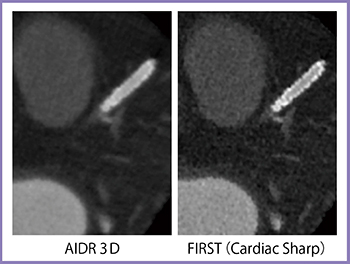

冠動脈CTAでは,AIDR 3DよりもFIRSTの方が石灰化や壁在血栓が明瞭に描出される(図3)。そして,驚くべきはステントの分解能で,FIRSTのCardiac Sharpで再構成を行うと,ストラットまで分離して描出される(図4)。頸動脈ステントの3D画像では,ステントのメッシュ構造まで観察することができる(図5)。

図4 冠動脈CTA(ステント)